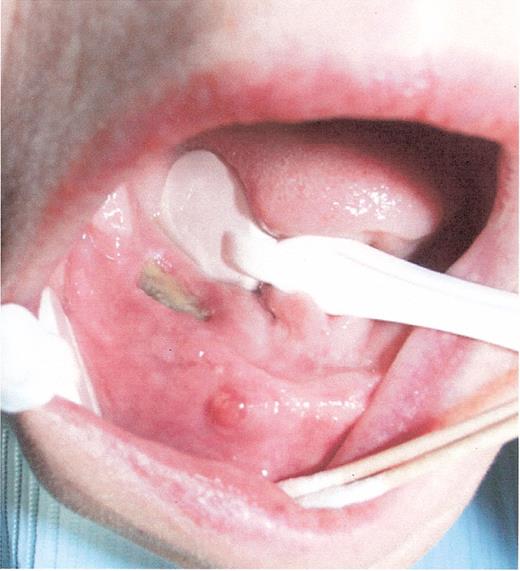

Stage I osteonecrosis of the jaw (ONJ). Patient with myeloma on zoledronic acid for 18 months.

Stage II osteonecrosis of the jaw (ONJ). Patient on zoledronic acid for 18 months.

Stage III osteonecrosis of the jaw (ONJ). Patient on pamidronate for 54 months followed by zoledronate for 18 months.